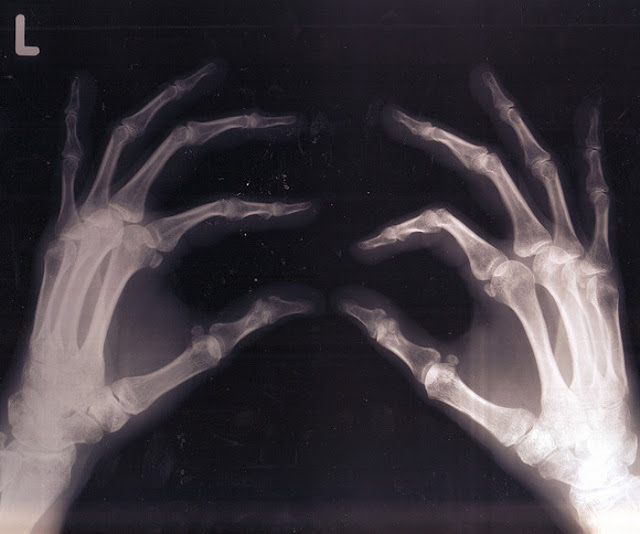

Source: Study: Marijuana Helps Heal Broken Bones & Even Makes Them Stronger | Humans Are Free